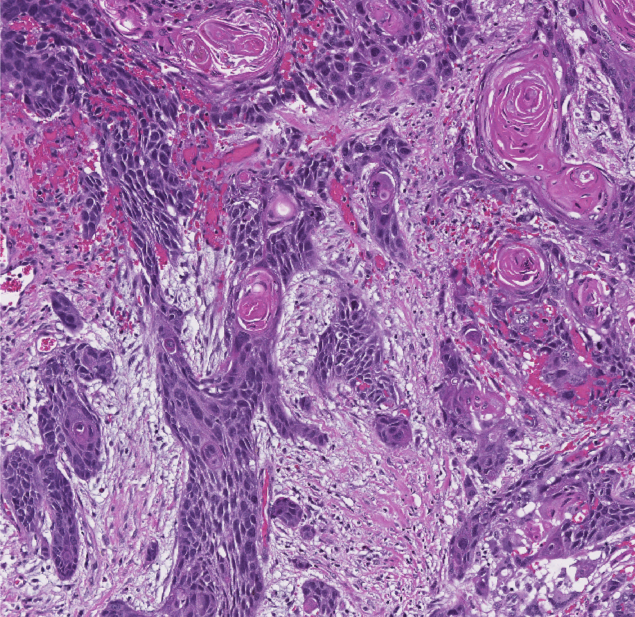

A 63-year-old man comes to the office due to several months of dysphagia, fatigue, occasional chest discomfort, and indigestion.  He has a history of hypertension and takes amlodipine.  The patient smokes 1 or 2 cigars daily.  His blood pressure is 140/80 mm Hg.  Physical examination is normal.  An endoscopic evaluation with esophageal biopsy is performed.  The histopathology of the specimen is shown in the image below. A 63-year-old man comes to the office due to several months of dysphagia, fatigue, occasional chest discomfort, and indigestion.  He has a history of hypertension and takes amlodipine.  The patient smokes 1 or 2 cigars daily.  His blood pressure is 140/80 mm Hg.  Physical examination is normal.  An endoscopic evaluation with esophageal biopsy is performed.  The histopathology of the specimen is shown in the image below.   Which of the following is the most likely cause of this patient's dysphagia? A) Benign tumor with slow growth B) Malignancy with probable poor prognosis C) Metaplasia with increased risk of adenocarcinoma D) Motor dysfunction with increased risk of carcinoma E) Reflux esophagitis with high risk of metaplasia Which of the following is the most likely cause of this patient's dysphagia?